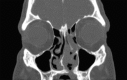

Eosinophilic angiocentric fibrosis (EAF) is an exceedingly rare and potentially disfiguring and obstructing benign lesion involving the upper airways. We report two cases of EAF originating from the nasal cavity in a 31-year-old female and a 58-year-old male exhibiting nasal obstructive symptoms, with imaging features and histopathology characteristic of EAF. Surgical excision was performed on one patient with a disfiguring nasal mass at a tertiary referral rhinology practice within a university centre. Summarized are the relevant clinical issues to increase awareness of this disease. The slow progression and rarity of the disease has previously resulted in diagnostic difficulty. We review the limited current literature surrounding the clinical features and treatment options for this progressive and potentially morbid condition. These cases reinforce that, while rare, inflammatory and fibrosing lesions in general should still be considered as part of the differential diagnosis in patients presenting with obstructive lesions in the sinonasal tract.